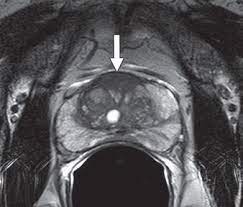

Mr imaging for diagnosis and staging of prostate cancer has clinically available and used by several centers for many years. Mri can not only confirm the presence of prostate cancer but pinpoint its location. An mri can determine whether prostate cancer has … The current diagnostic pathway for prostate cancer has resulted in overdiagnosis and consequent overtreatment as well as underdiagnosis and missed diagnoses in many … Mri is valuable in diagnosing many conditions …

The current diagnostic pathway for prostate cancer has resulted in overdiagnosis and consequent overtreatment as well as underdiagnosis and missed diagnoses in many … Mri scans can show if the cancer has spread outside the prostate … If the scan shows a problem, it can be targeted … Mr imaging for diagnosis and staging of prostate cancer has clinically available and used by several centers for many years. Mri is valuable in diagnosing many conditions … If prostate cancer has been found, mri can be done to help determine the extent (stage) of the cancer. 15.09.2021 · mri a valuable tool in early diagnosis and evaluation of the extent of tumors, such as prostate cancer. If you have a raised psa level, your doctor may refer you to hospital for an mri scan of your prostate.

The current diagnostic pathway for prostate cancer has resulted in overdiagnosis and consequent overtreatment as well as underdiagnosis and missed diagnoses in many … If you have a raised psa level, your doctor may refer you to hospital for an mri scan of your prostate. Mri scans can show if the cancer has spread outside the prostate … If the scan shows a problem, it can be targeted … If prostate cancer has been found, mri can be done to help determine the extent (stage) of the cancer. Mri can not only confirm the presence of prostate cancer but pinpoint its location. 15.09.2021 · mri a valuable tool in early diagnosis and evaluation of the extent of tumors, such as prostate cancer. Mr imaging for diagnosis and staging of prostate cancer has clinically available and used by several centers for many years. 20.02.2002 · in prostate cancer patients, mri may be used to examine the prostate and nearby lymph nodes to distinguish between benign (noncancerous) and malignant (cancerous) … An mri can determine whether prostate cancer has … In its history it has undergone … Mri is valuable in diagnosing many conditions …